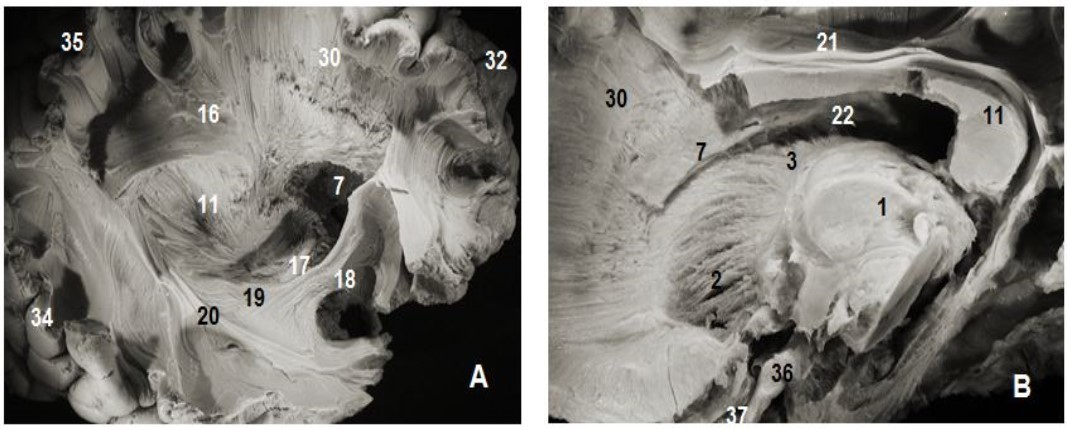

Figure 2.Subependymal stratum: (A) lateral view of right hemisphere and (B) medial view of left hemisphere. 1.Thalamus, 2. Anterior thalamic radiation, 7. Subependymal substratum, 4. Ependymal membrane, 6. Lateral ventricle, 11. Splenium of corpus callosum, 21. Cingulum, 30. Corona radiata, 32. Parietal pole, 33. Frontal pole, 35. Occipital pole, 36 tract optic

Figure 3.Thalamic radiations: (A) lateral view and (B) medial view. 1. Thalamus, 2. Anterior thalamic radiations, 3. Superior thalamic radiations, 4. Posterior thalamic radiations, 5. Inferior thalamic radiations, 6. Ventricular landmark, 10. Tapetum of corpus callosum, 11. Splenium of corpus callosum, 22. Ependymal membrane, 23 .Pons , 24. Mesencephalon, 17. Optic tract, 18. Uncinate fasciculus, 31. Occipital pole, 36. Cerebellum, 37.Frontal pole.

The C-shaped uncinate fasciculus (UF) connects the frontal and temporal lobes. The uncinate fasciculus (Figure 2, Figure 4) is composed of 3 parts: a fanning frontal end, an insular segment where the fibers are grouped together and a polar temporal extremity. The insular segment was discovered after the removal of the insular cortex laterally, the extreme capsule medially which consists of arcuate fibers connecting the insula to the opercula except the portion near the falciform fold. The last plane was exposed after the ablation of the claustrum and the extreme capsule which are below the tip of the insular cortex which is lateral to the limen insulae and medial to the claustrum. At this level, the posterior and superior margins were closely attached th lower edge of the inferior occipito frontal bundle. The detachment and excision of this fasciculus exposed the frontal and temporal rapports of the uncinate fasciculus.

The inferior occipitofrontal fasciculus (Figure 2, Figure 4) closely attached to the previous fasciculus was composed of fiber bundles connecting the frontal lobe to the temporal, posterior parietal and occipital lobes. The IOFF is shaped somewhat like a flattened tape and is composed, as the uncinate fasciculus, of three parts: frontal, insular and parietal temporo-occipital segments.

The sub-ependymal stratum also known as the subcallosal stratum was made of a fiber-free layer of white matter. This layer of white matter was exposed after excision of the ependymal layer lining the ventricular system. It is located between the caudate nucleus and callosal radiations (Figure 1, Figure 2, Figure 4). Under the ependyma backward to the occipital horns, callosal fibers form together the tapetum and thalamic radiations. Our dissection failed to show a precise boundary between the tapetum and the sub-ependymal stratum. The substratum is a sub-ependymal structure located between the caudate nucleus, the corpus callosum radiations and the internal capsule. Globally, it is located below the ependyma and medial to the cingulum. It is not made of fibers connecting the frontal and the occipital lobes.